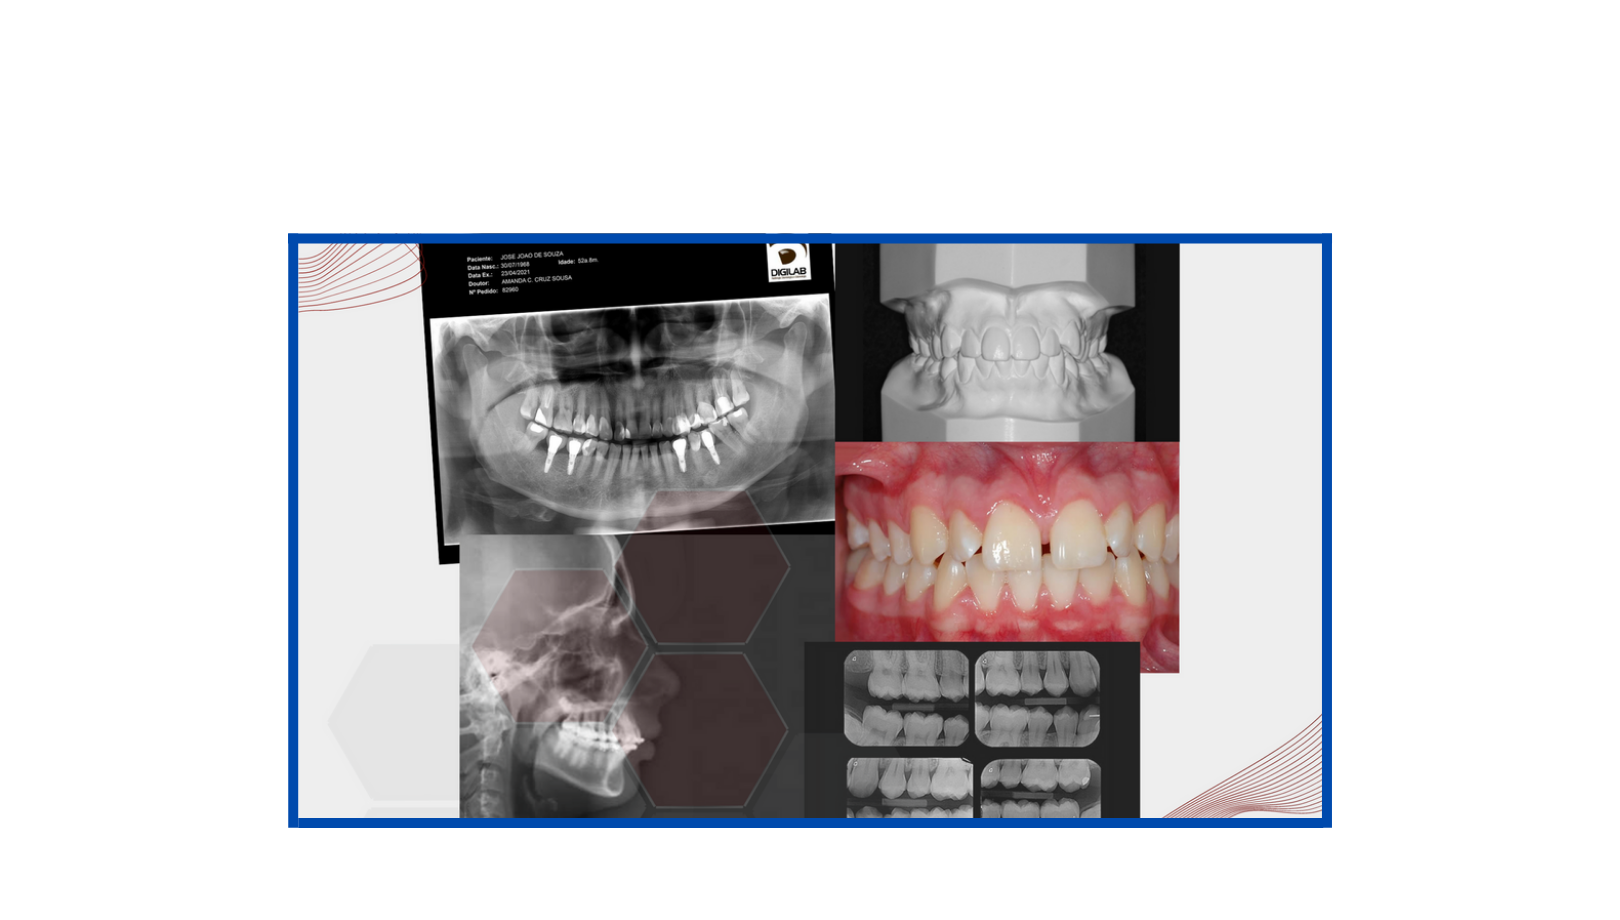

Documentações Ortodônticas

A documentação ortodôntica é um conjunto de exames composto por radiografias, fotografias intra e extra-bucais, modelos em gesso das arcadas dentárias, análises cefalométricas e de modelos computadorizados que o dentista solicita para ter uma visão abrangente e detalhada do caso de seu paciente.